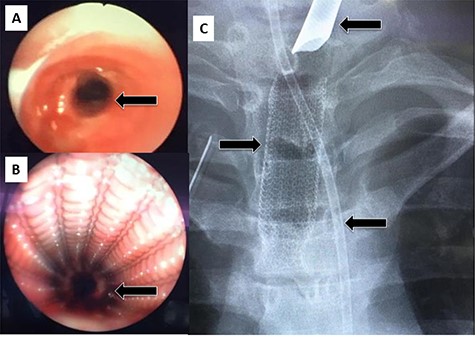

After discharge, the patient presented to the Emergency Room with shortness of breath and tachypnea. Chest X-rays and CT scan were unremarkable; however, he was admitted with type 2 respiratory failure and placed on noninvasive ventilation. Due to persistent tachypnea, the patient’s initial CT scans were reassessed with reconstruction and showed a complete transection of the trachea that was overlooked initially (Fig. 2). Flexible bronchoscopy revealed a significant post-traumatic tracheal stenosis (Fig. 3). It was tight stenosis (2 cm length on the CT reconstruction) and just above the carina. The patient was taken to the OT, with the ECMO team on standby. During rigid bronchoscopy, the patient became more hypoxic, and VV-ECMO was instituted. The stenosis was dilated with a small (#6) endotracheal tube (ETT) placed across the stenosis. He subsequently returned to the OT for further dilation and placement of a # 7.5 ETT. After 9 days, bronchoscopy revealed no gross residual stenosis and therefore the patient was successfully extubated. The patient was removed from ECMO support on the following day. After several days, the patient developed tachypnea, tachycardia and a respiratory acidosis. He was reintubated and shifted to the OT again (with ECMO standby) for redilation of restenosis with a #8 ETT in place. A covered tracheal stent was placed intraoperatively via rigid bronchoscopy (Fig. 4 A–C). Later on, the patient was extubated and eventually discharged home in stable condition.

(A) Rigid bronchoscopy show 4 mm stenosis of the distal trachea, (B) intra-tracheal showing the stent following dilatation and placement of stent, (C) plain X-ray showing stent in place, feeding tube and endotracheal tube.